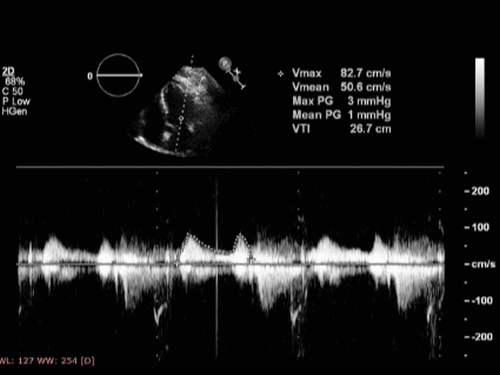

Проводимая же эхокардиография с допплеровским анализом позволяет определить скорость движения крови и турбулентность кровотока. Полученные данные могут нести информацию о пороках, наполнении левого желудочка. Основой допплеровских измерений является расчет изменения скорости движения объекта по отношению к изменению частоты отражаемого сигнала. При столкновении звука с движущимися эритроцитами частота меняется. Допплеровским сдвигом называют величину подобного изменения. Обычно этот сдвиг находится в рамках воспринимаемых человеком звуков и может воспроизводиться эхо-аппаратом в виде слышимого сигнала.

Площадь поперечного сечения отверстия митрального клапана составляет примерно 5,0 см2, что позволяет наполнению левого желудочка происходить преимущественно в раннюю диастолу (примерно две трети объема поступающей крови) с максимальной скоростью по эхокардиографии 50-100 см/с. Оставшаяся треть ударного объема проходит через митральный клапан во время систолы предсердий. Во время диастаза объем желудочков остается неизменным. При упражнениях и увеличении частоты сердечных сокращений диастаз укорачивается, а компоненты раннего и позднего наполнения сближаются, пока они не объединятся и не станут неразличимы на допплерографии. С возрастом картина наполнения меняется на противоположную, и доминирующее наполнение левого желудочка происходит в позднюю диастолу.

Эхокардиография в М-режиме

M-режим на эхокардиографии (M от английского слова «motion» означает движение) исследует сердечные структуры только вдоль одной оси (представьте себе «ледоруб» или «игольчатая биопсия») с тканевыми интерфейсами, представленными в виде точек на экране дисплея. Чтобы показать модели движения, добавляется линейная развертка, что приводит к графическому отображению, как показано на рисунке. M-режим на эхокардиографии может быть более трудным для понимания неспециалистом, но он по-прежнему актуален из-за его высокого временного разрешения (1000 линий с −1 по сравнению с 25 для двухмерного изображения), которое имеет лучшую развертку по времени, а также тот факт, что несколько сердечных циклов могут отображаться на одном изображении.